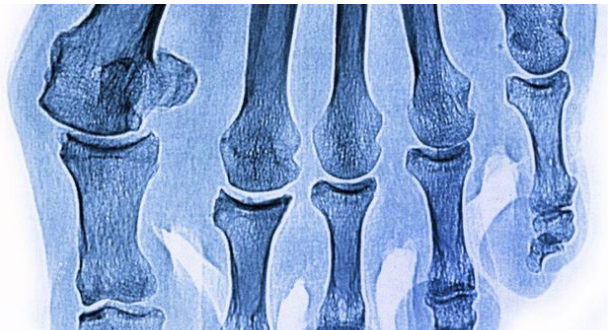

İşte kırıklar hakkında doğru bildiğimiz 5 yanlış! - Resim: 1

KIRIK OLSA KIMILDATAMAZSIN SÖZÜ YANLIŞ Vücudumuzda kırık olduğunu hissettiğimiz bir bölgenin kırık olup olmadığını anlamak için halk tarafından çözüm yöntemi olan, "Oynatabiliyor musun?", "Oynatabiliyorsan kırık yoktur." sözlerini duymayan yoktur. Oysa kırık bir kemiği kımıldatmak mümkündür. Bu sorular kemikte çatlak olup olmadığını anlamada bir kriter değildir. Kırığın üç belirtisi ağrı, şişme ve şekil bozukluğudur. Ayrıca olay anında kırılma sesi duymak da mümkündür.